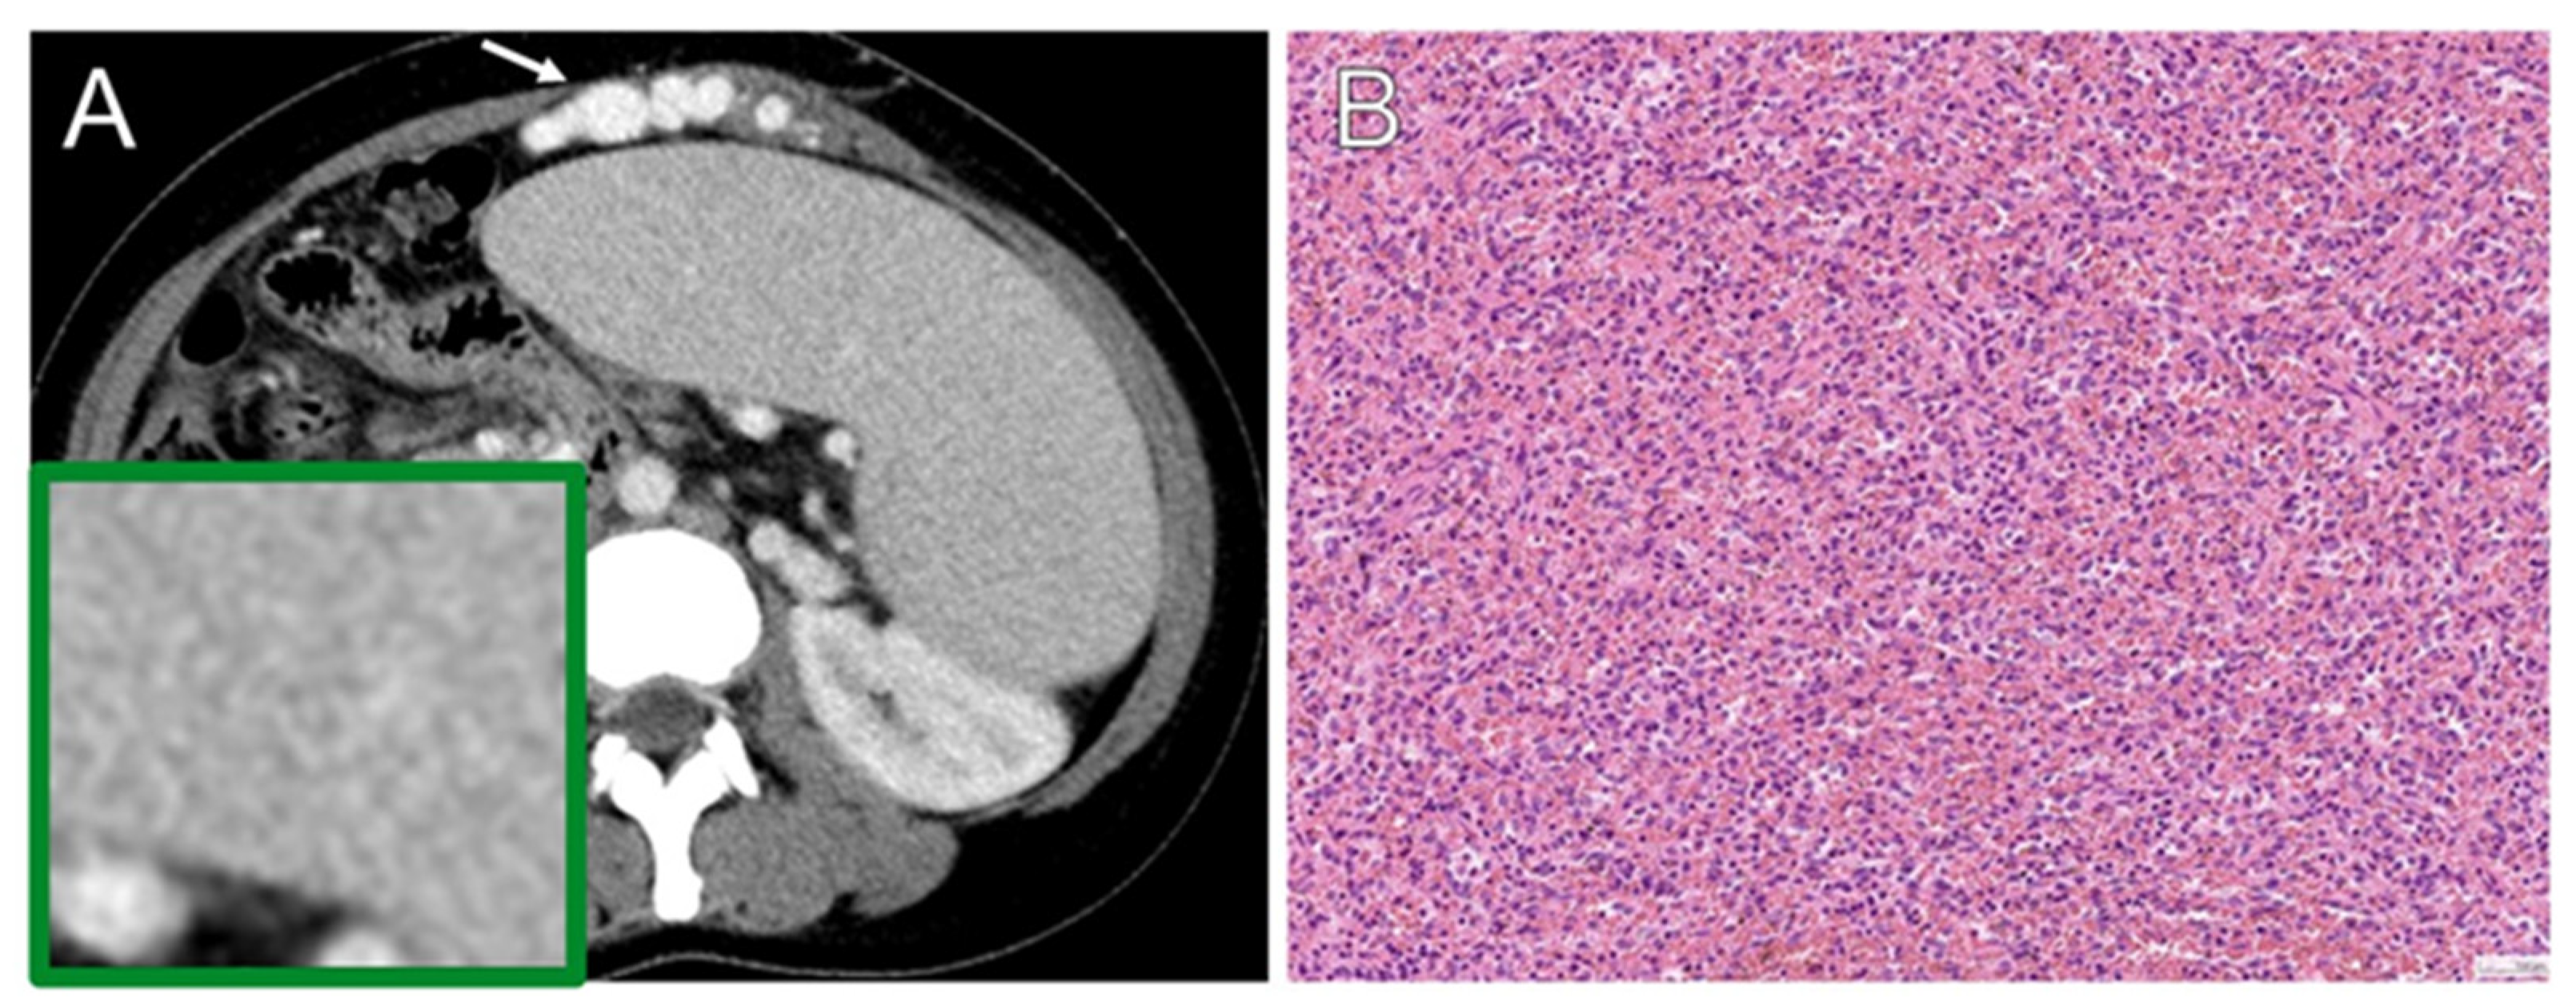

3.5. Histopathology